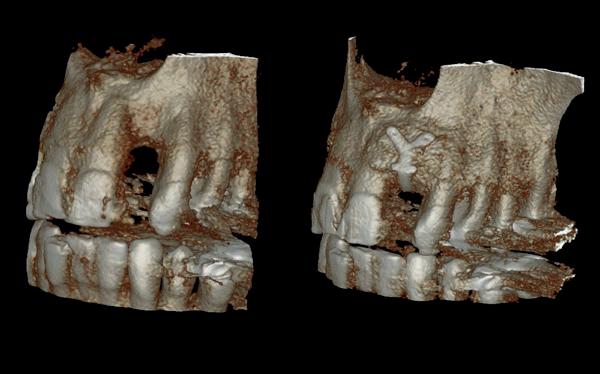

Bij klinisch en röntgenologisch onderzoek viel echter op dat radix van de 12 en 22 een convergerende (de radices staan dan naar mesiaal en naar elkaar toe) in plaats van divergerende (radices staan dan van elkaar af) stand had. Door deze convergerende stand van de radices was er in mesio-distale zin geen ruimte voor twee implantaten ter plaatse van de 11 en 21. Er werd daarom besloten, in tegenzin

1. Retainer met twee frontelementen

2. OPT radices 12 en 22 convergeren

3. Vaste apparatuur voor torque 12 en 22

4. OPT radices 12 en 22 divergeren na orthodontische behandeling

van de patiënt, om eerst weer vaste apparatuur terug te plaatsen om de radices in een divergerende stand te plaatsen. Gelukkig verliep deze behandeling voorspoedig. (afbeelding 2 -4). Het volgende behandelplan werd gemaakt: